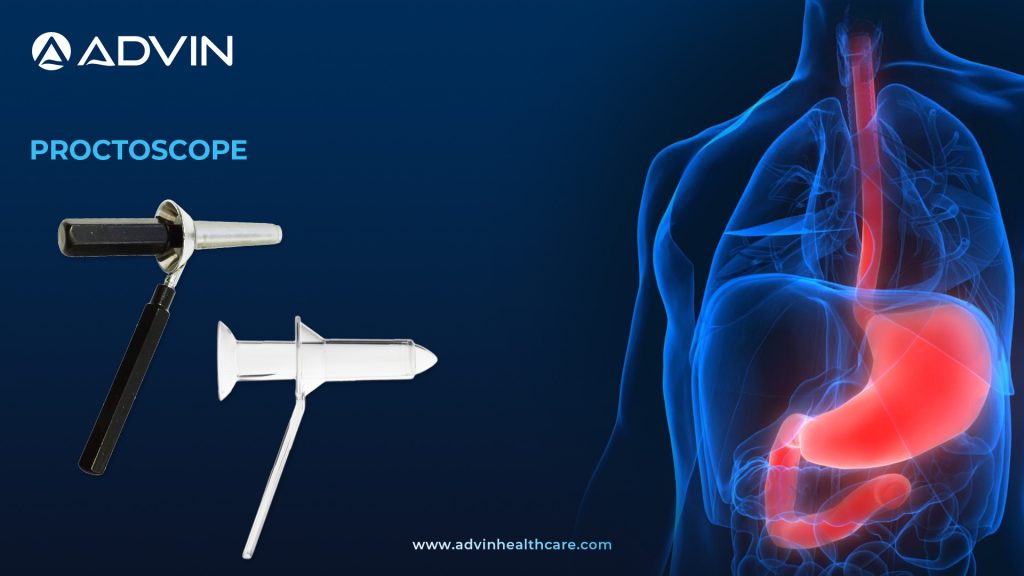

Understanding the Proctoscope – A Vital Tool in Colorectal Examination

Basic Overview of the Proctoscope A Proctoscope is a medical instrument used to examine the anal canal, rectum, and lower part of the colon. It is a hollow, rigid tube made from either stainless steel or medical-grade plastic. The device allows doctors to visually inspect and diagnose issues in the...